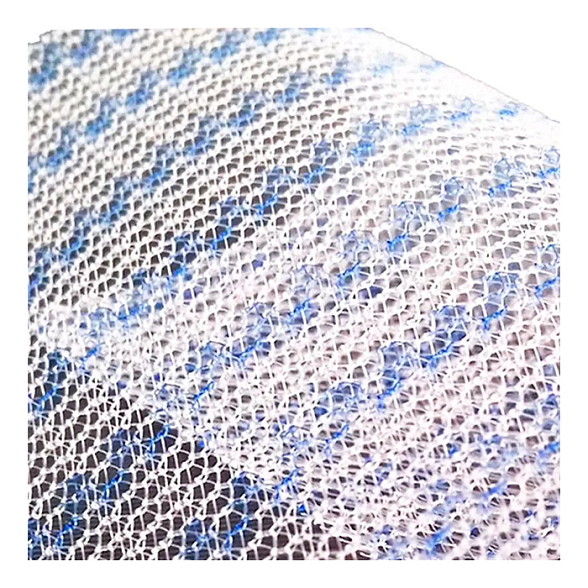

Эндопротез-сетка (сетка хирургическая) полипропиленовый для восстановительной хирургии ЭСФИЛ тяжелый, 8х12 см, Линтекс

Эндопротез-сетка полипропиленовая ЭСФИЛ тяжелый для восстановительной хирургии

Представляем вашему вниманию высококачественный хирургический имплантат — эндопротез-сетку полипропиленовую ЭСФИЛ тяжелый от известного производителя «Линтекс». Это современное решение для пластики и укрепления тканей в абдоминальной и тазовой хирургии, разработанное для обеспечения надежного и долговечного результата.

Сетка ЭСФИЛ тяжелый размером 8х12 см — это монофиламентный полипропиленовый сетчатый эндопротез с увеличенной плотностью и массой. Его ключевая особенность — высокая механическая прочность при минимальной ригидности, что позволяет эффективно закрывать обширные дефекты тканей, обеспечивая физиологичное и анатомичное восстановление.

- Отличная интеграция с тканями: Макропористая структура монофиламентной сетки способствует свободному прорастанию соединительной ткани, обеспечивая прочное сращение и снижая риск осложнений.

Благодаря макропористой структуре (размер пор более 75 мкм) сетка свободно инфильтрируется макрофагами, фибробластами и коллагеновыми волокнами. Это приводит к образованию прочного соединительнотканного рубца, который и составляет основу несущего каркаса.